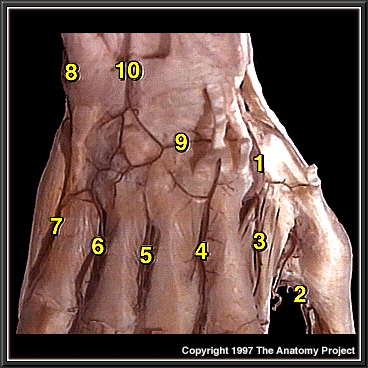

Dorsum of the hand, deep dissection, posterior view

Radial artery

Arteria princeps pollicis

1st dorsal metacarpal a.

2nd dorsal metacarpal a.

3rd dorsal metacarpal a.

4th dorsal metacarpal a.

Dorsal digital artery to 5th digit

Dorsal carpal branch of ulnar artery

Dorsal carpal branch of radial artery

Anastomosis between anterior and posterior interosseous arteries